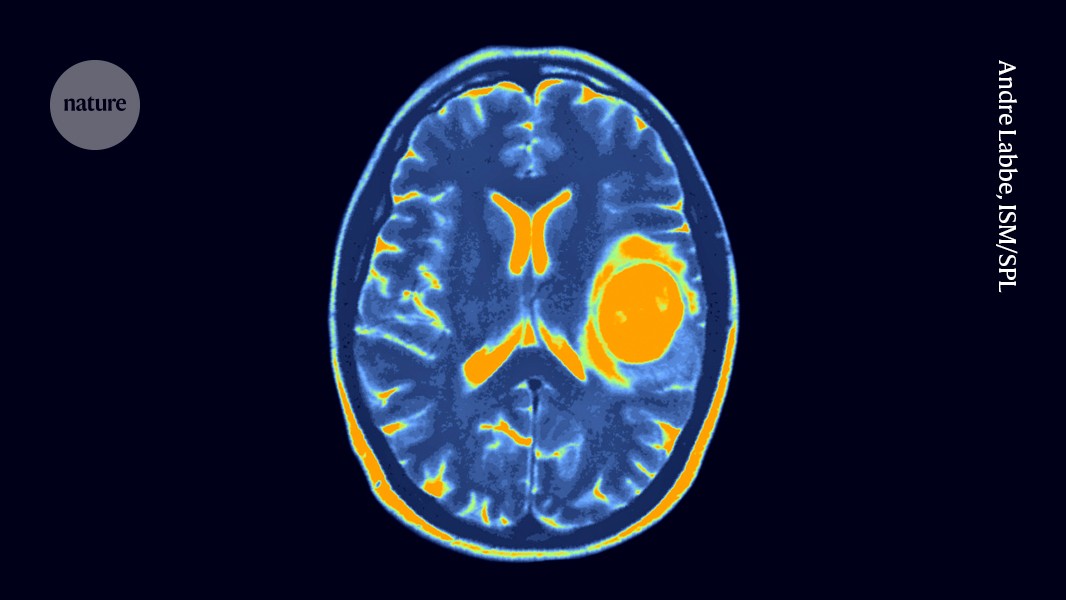

A brain tumour called a glioblastoma (orange; artificially coloured). Researchers are now trialling engineered immune cells against these deadly tumours and others called diffuse midline gliomas.Credit: Andre Labbe, ISM/Science Photo Library